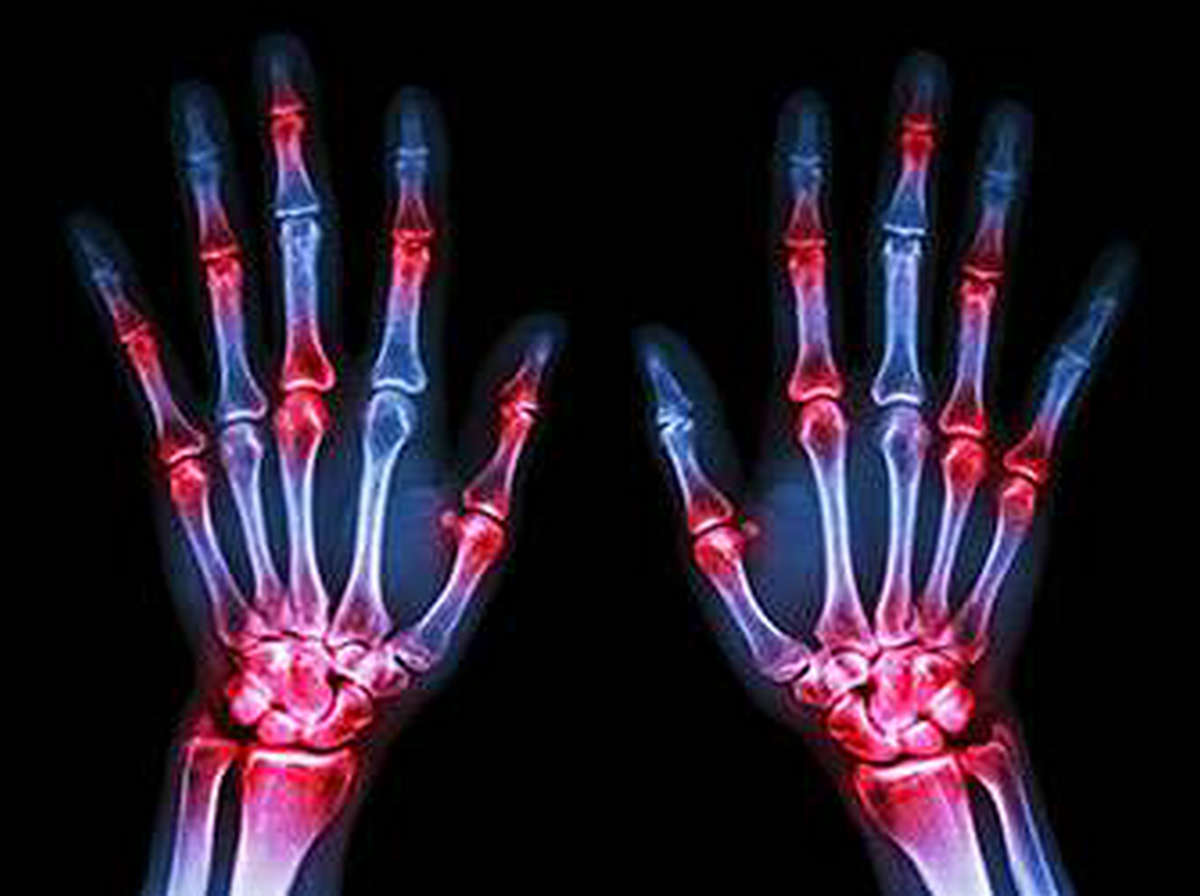

类风湿关节炎是一种进行性的全身性自身免疫性疾病,全世界每100人中至少有1人患有此病。由于一些不为人知的原因,每4名患者中就有3名是女性。虽然其最明显的特征是疼痛、僵硬、炎症和关节功能的最终恶化,患者患心血管疾病和其他炎症并发症的风险也更高。